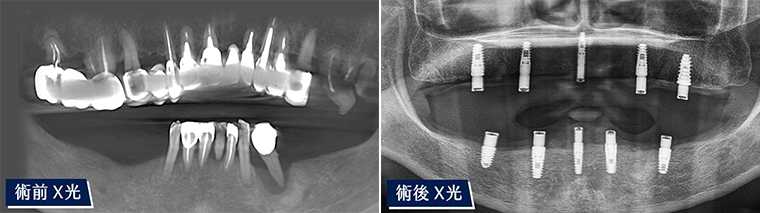

令人驚喜! 細緻又自然的全口重建

張小姐牙齒的問題拖了很長的時間,經過檢查發現牙齒的狀況相當糟糕。醫師與張小姐詳細討論適合的方案,並透過3D全口掃描規劃,最終製作出美麗又自然的假牙。